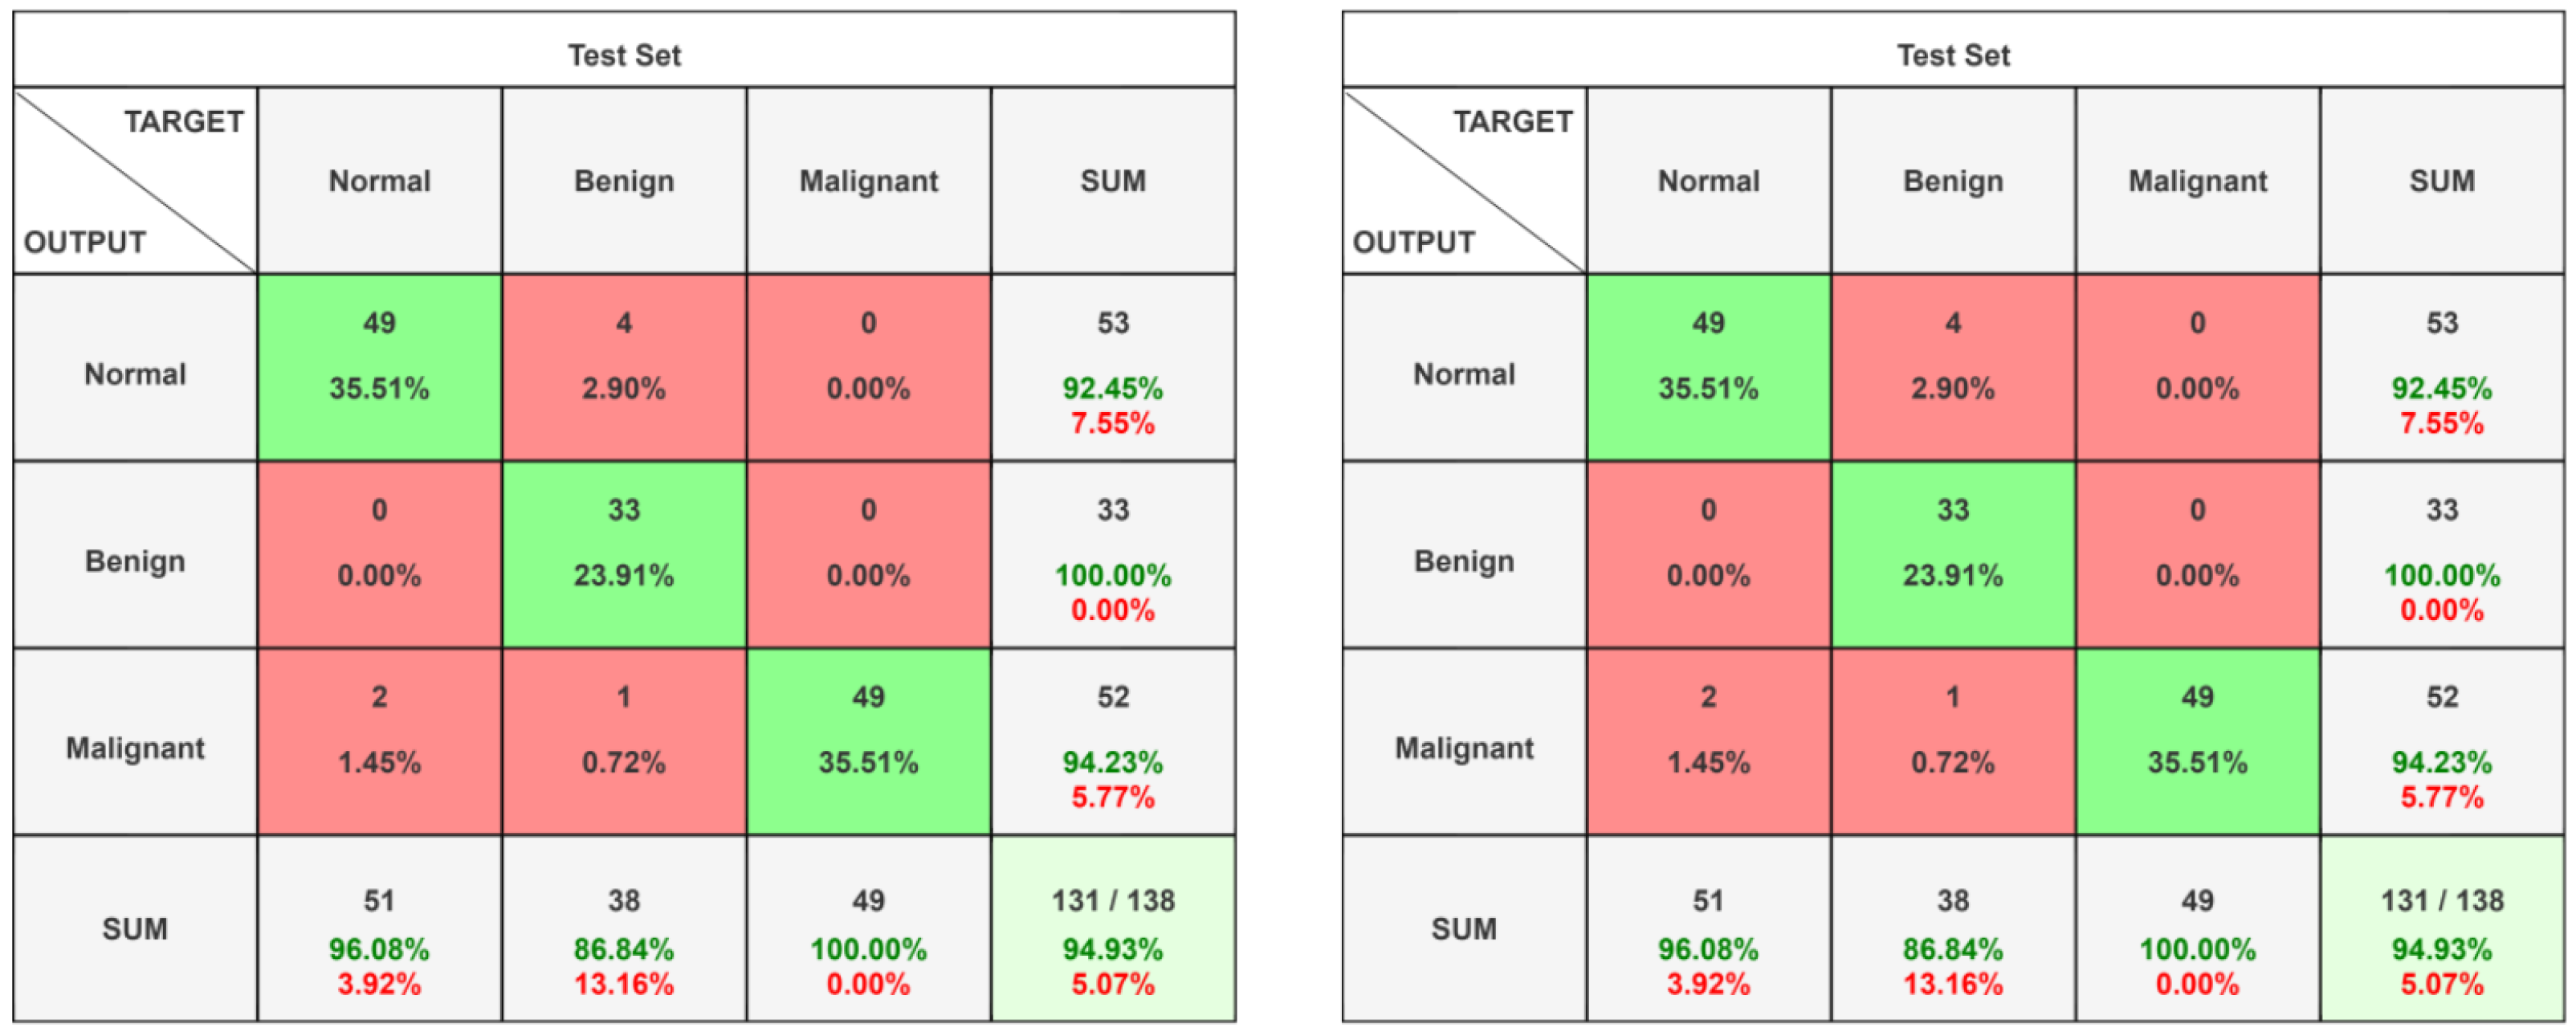

4.1. Confusion Matrix

5.1. Classification